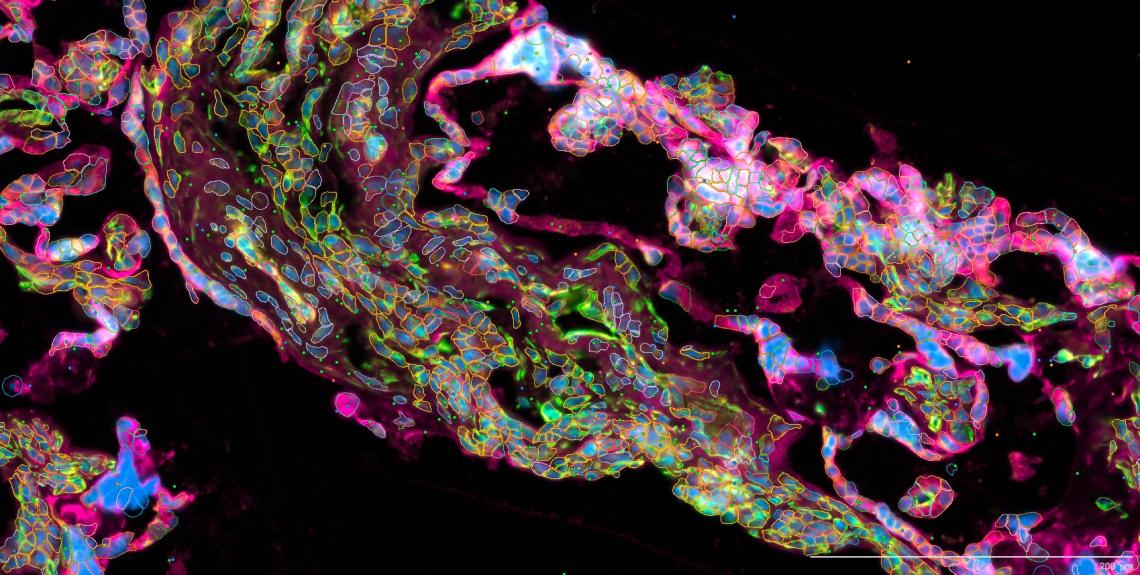

Environmental Health: Investigating the Impact of Micro- and Nanoplastic (MNP) on Maternal-Fetal Health and Adverse Pregnancy Outcomes

- Aim: To quantify MNP bioaccumulation in the placenta and its correlation with preterm birth.

- Techniques: Pyrolysis-gas chromatography/mass spectrometry (Py-GC/MS), spatial multiomics.